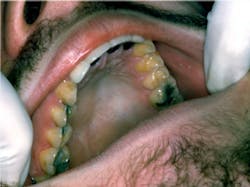

Your new patient today is Rodney. He is 47 years old and has come to your clinic because he says “his teeth need to be cleaned.” He says that he probably needs some additional dental work completed (see Figure 1) since he began some restorative work with his previous dental providers. He is complaining of sensitivity and a constant bad taste.

As you review his medical history, he states that he has decreased his use of over-the-counter antacids after taking them several times a day for a period of at least 10 years. As you begin your examination, you note the erosion on most surfaces of his teeth.

Two possibilities are considered. The first consideration is an eating disorder, and this type of erosion usually is found on the lingual surfaces of the teeth. But the patient denies any problem with disordered eating now or in the past.

The second consideration would be chronic long-term gastroesophageal reflux disease (GERD). After referral and diagnosis, Rodney does indeed suffer the effects of GERD. After many years of this chronic disease, the sensitivity/burning may actually decrease as the tissue becomes damaged, affecting the sensitive fibers, and this has occurred in Rodney’s case.